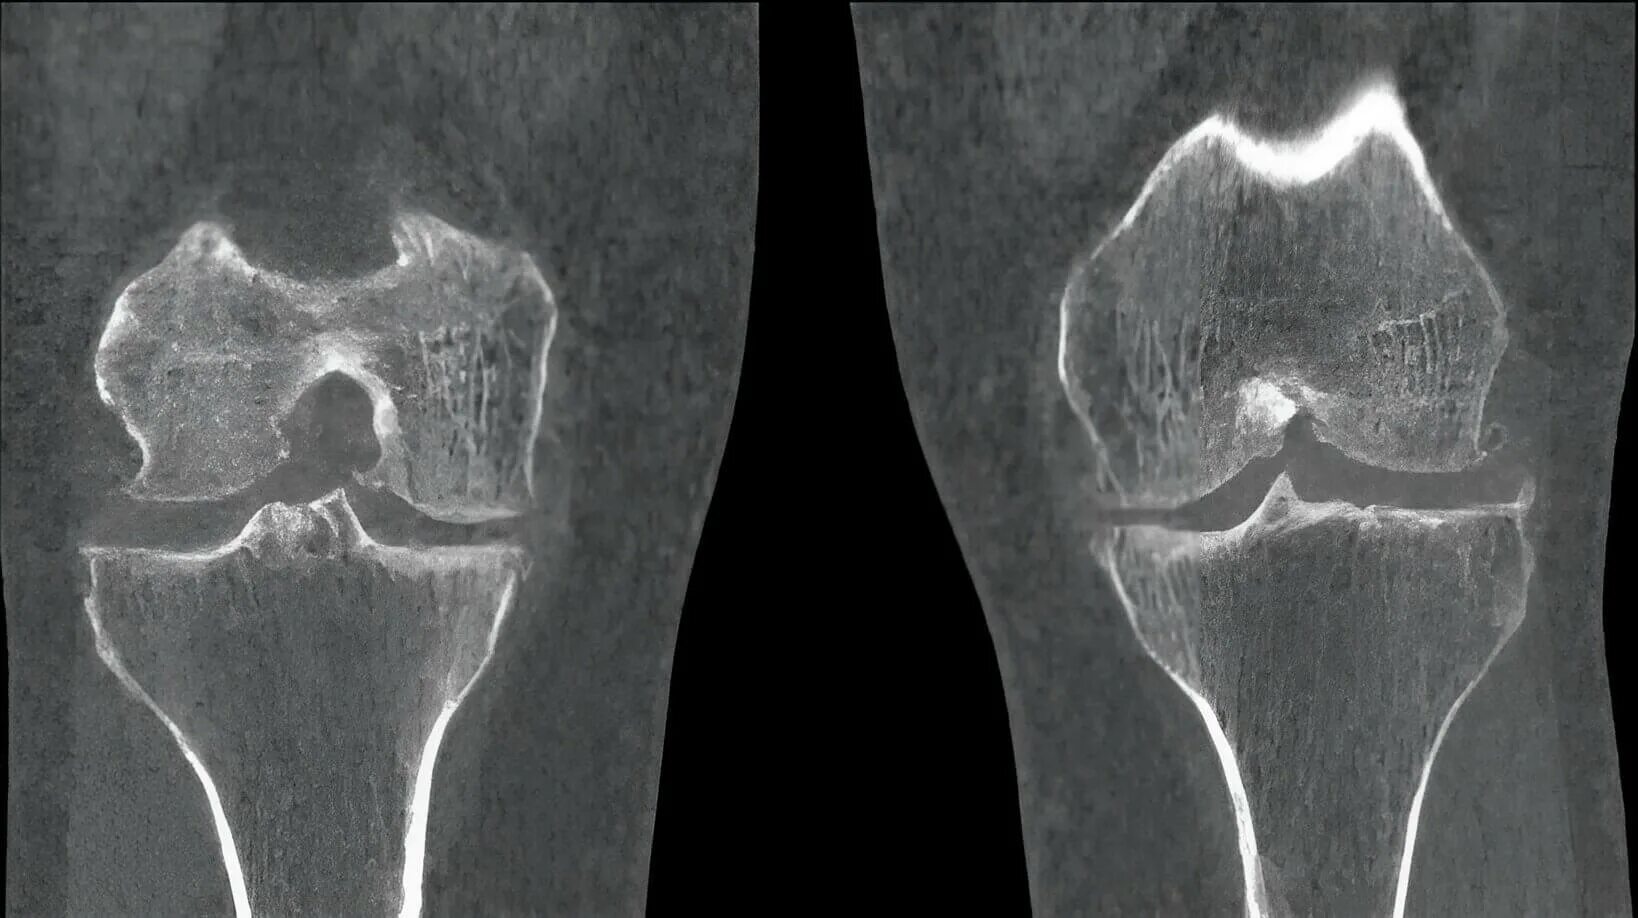

Гонартроз мрт